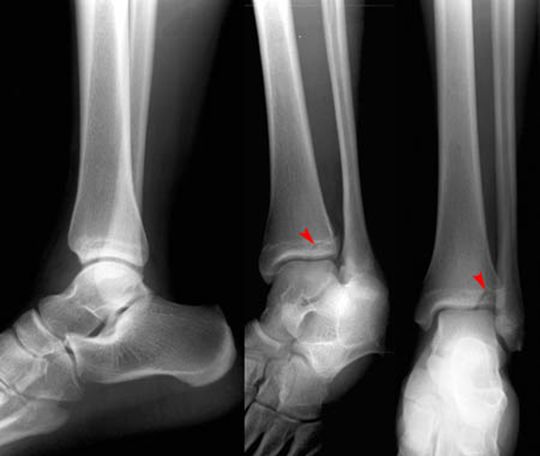

Maisonneuve Fracture

腓骨中段骨折

下胫腓分离

正常踝关节

踝关节骨折

三踝骨折

踝关节脱位